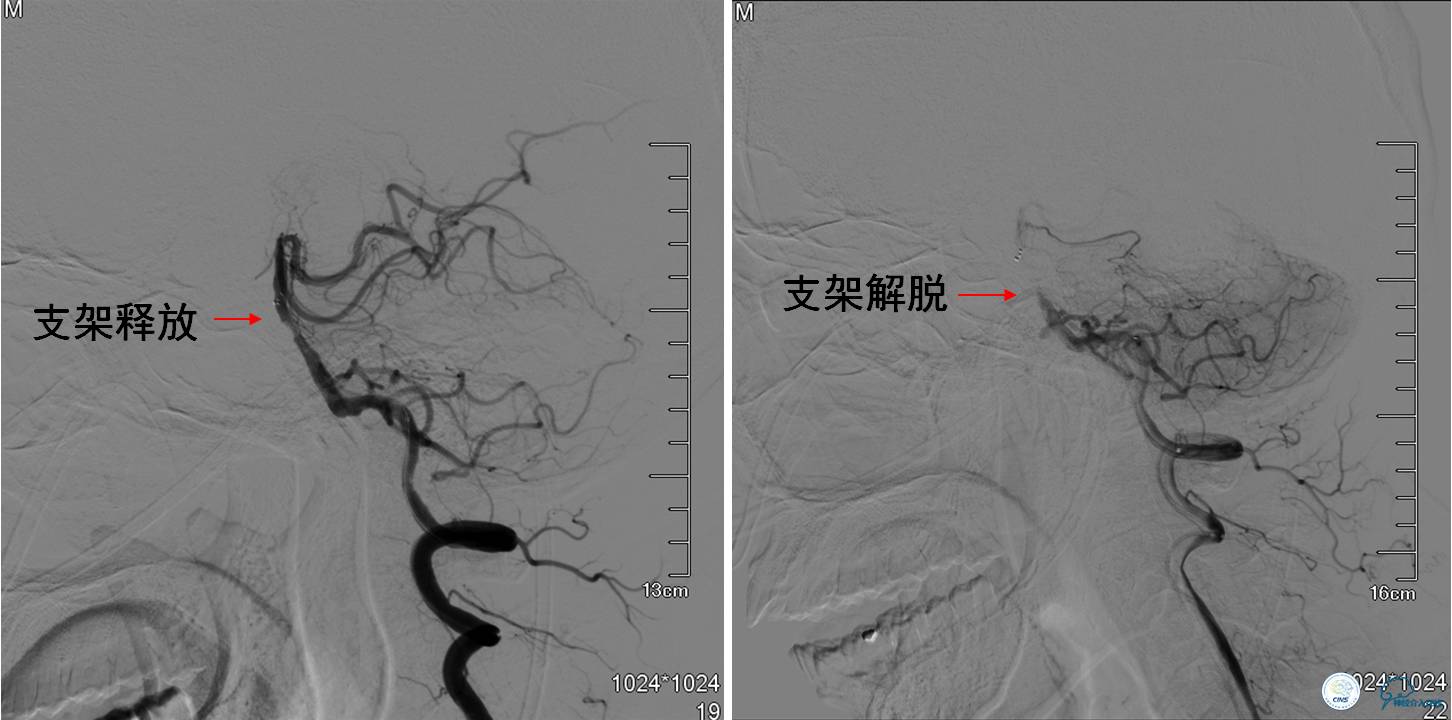

▼球囊扩张后:狭窄明显改善。

▼支架解脱后:出现支架内急性血栓形成。

Q:支架内急性血栓的处理?

》2015年《缺血性脑血管病介入治疗抗血小板策略中国专家共识》:术中出现急性血栓形成,可使用替罗非班,起始推注剂量为10ug/kg,在5min内经动脉导管推注完毕,然后以0.15ug·kg-1·min-1的速率静脉维持16—24小时。

》该患者在10min内两次予以替罗非班0.5mg缓慢推注,但前向血流仍不能改善。

▼再次球囊扩张:球囊扩张后,狭窄改善,术中等待30min后再次造影显示血管未再狭窄或闭塞,手术结束。